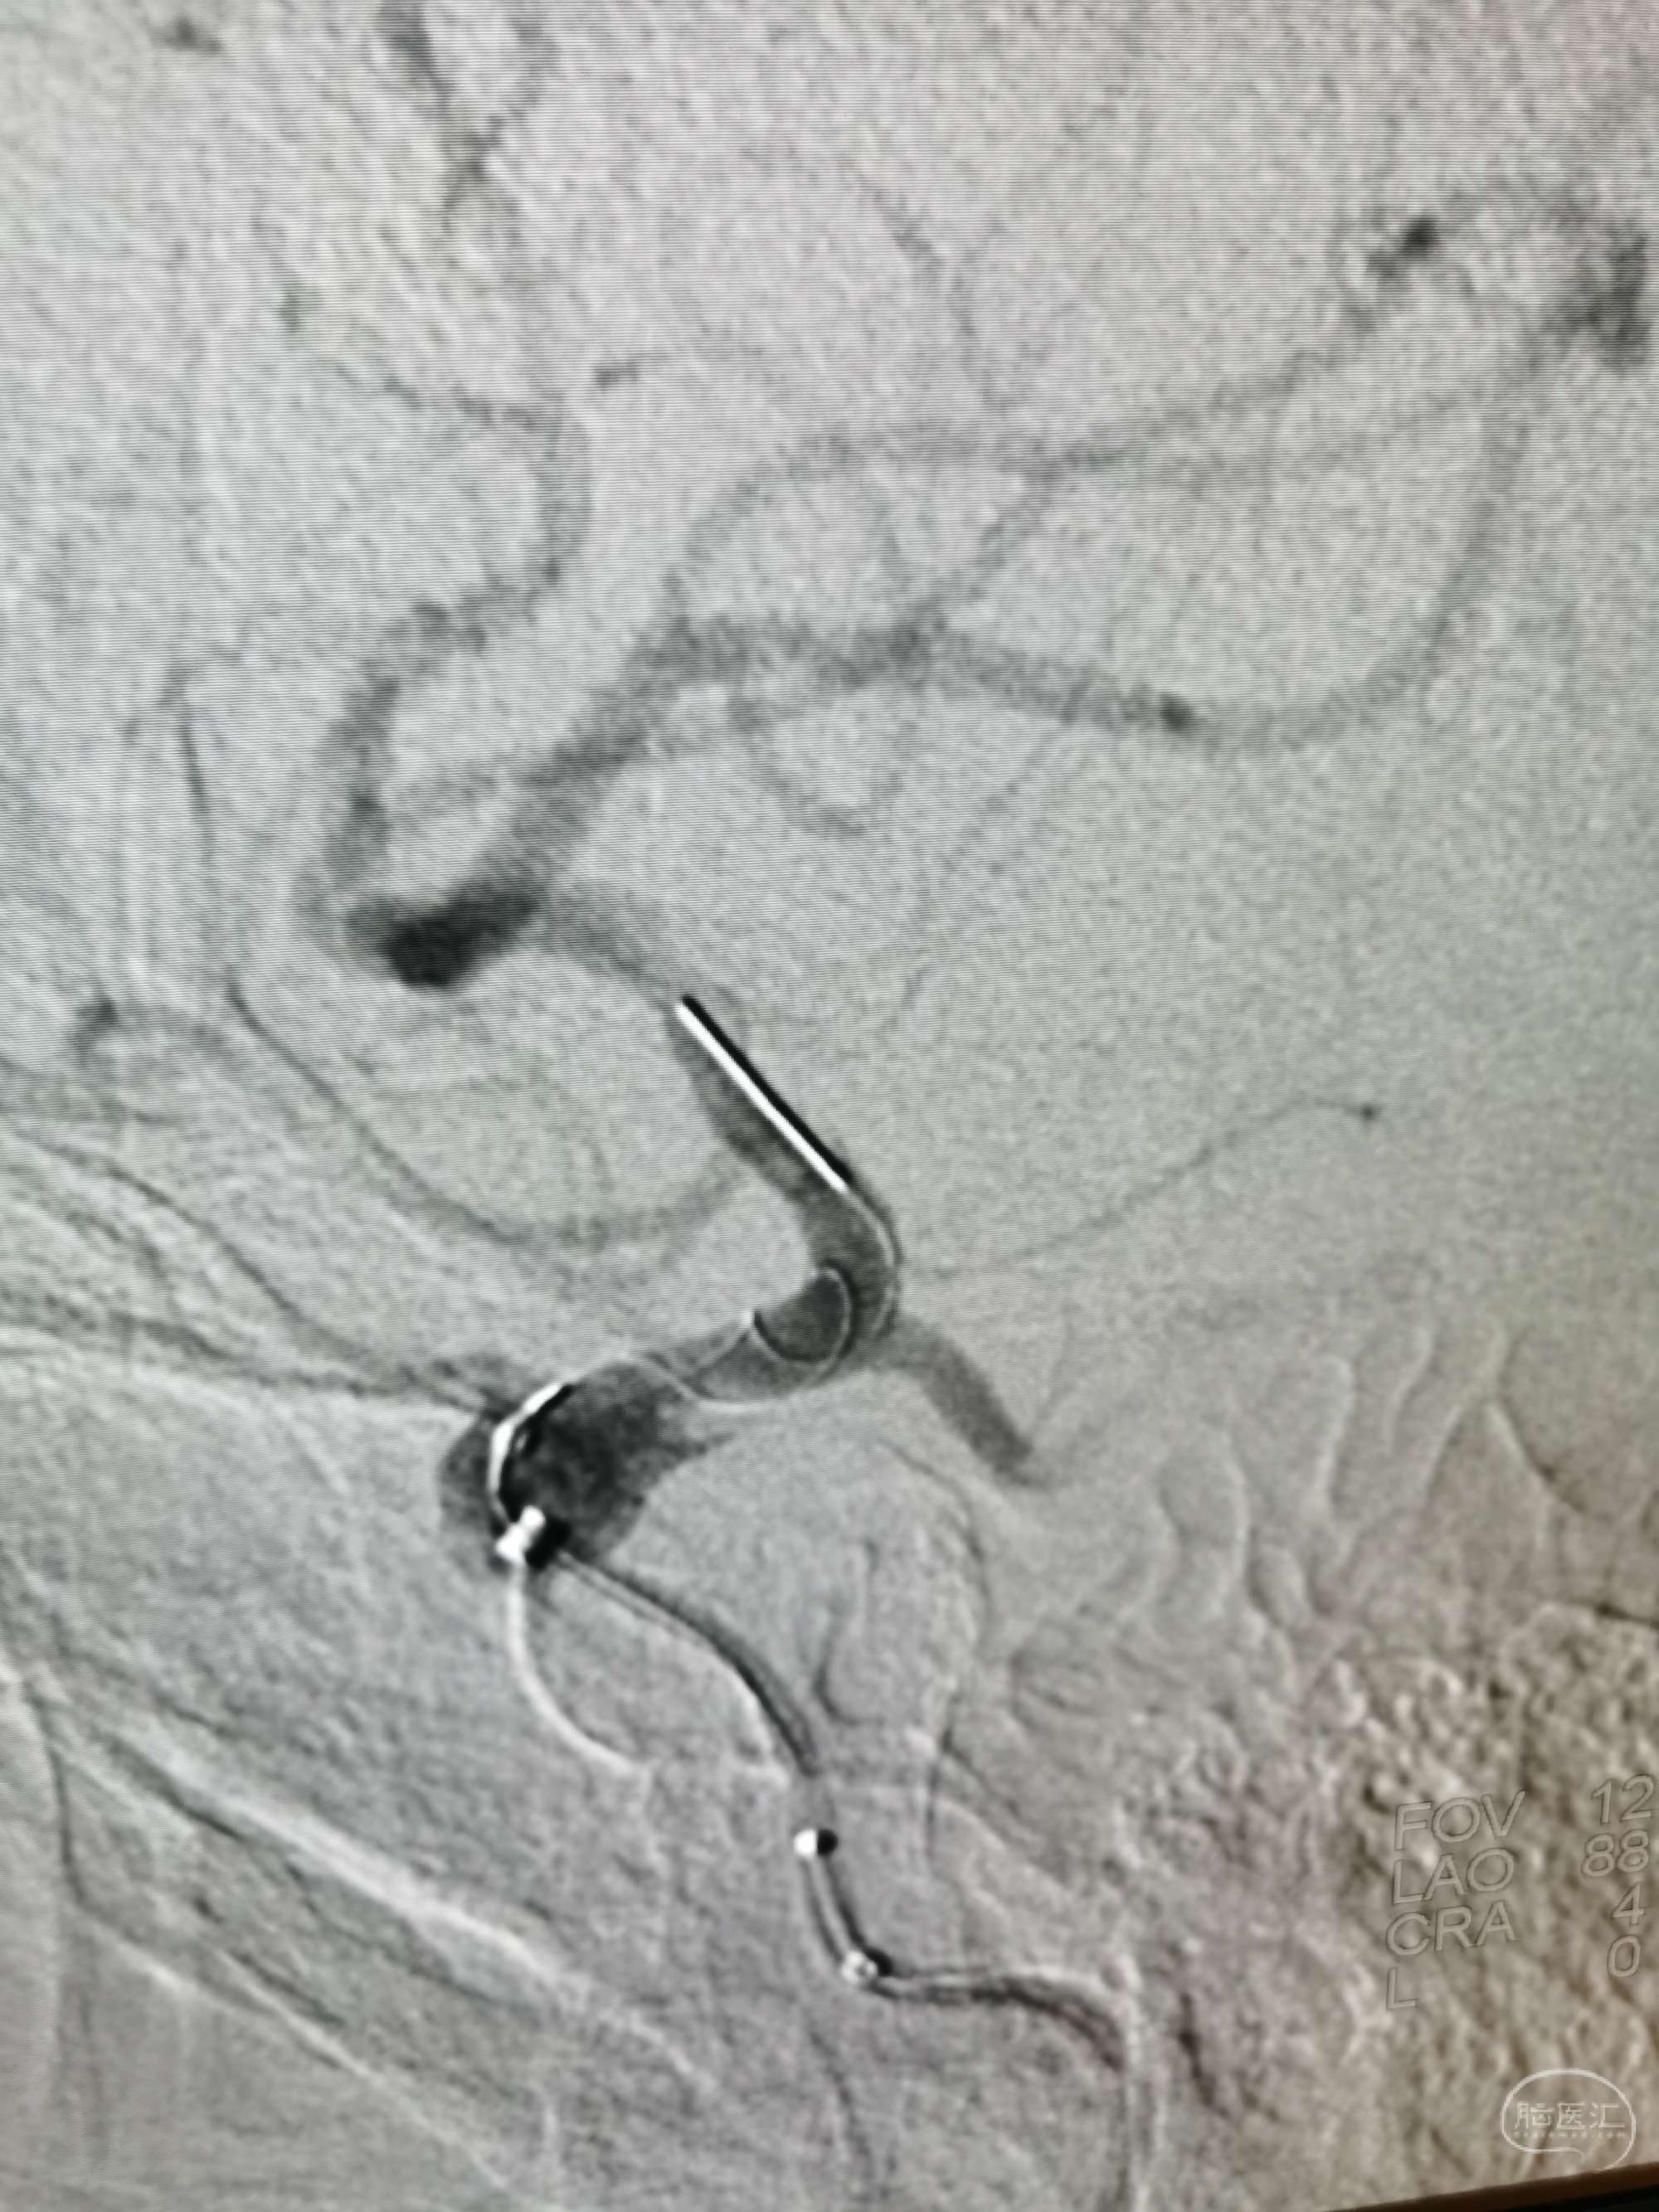

密网支架导管到位。

放置Tubrige4.0x30mm支架。

非减影像示支架打开良好。

支架后DSA示:载瘤动脉通畅。

支架CT:显示支架贴壁良好。